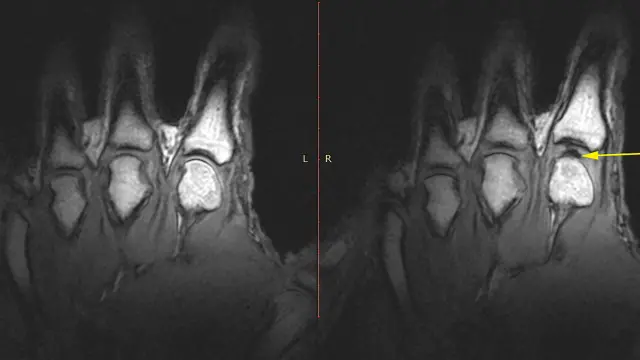

Para ilmuwan menggunakan pemindai kedokteran untuk mencoba menangkap setiap bunyi "kertak".

Percobaan ini menggunakan teknologi pemindaian MRI.

Berdasarkan scan, tidak terdapat tanda-tanda gelembung gas yang keluar atau menghilang.

Jadi gelembung tetap di tempat itu bahkan setelah suara gemeretak terjadi, tetapi hal ini tersembunyi dari penglihatan ketika jari-jari kembali ke posisi normal.